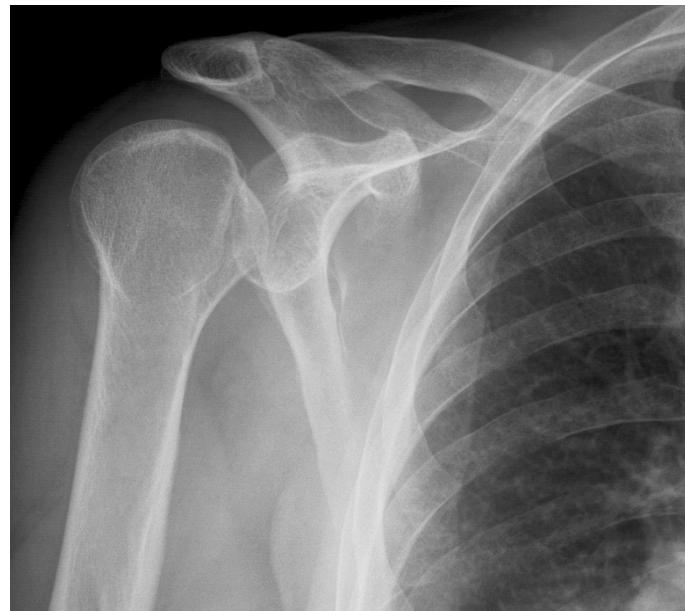

Imaging

Case Study 3: Posterior Shoulder Dislocation

A 29-year-old male with known seizure disorder presented in the ER complaining of left shoulder pain for 2 weeks.

History

- Mechanism of injury: Preceded by seizure, patient non-compliant with medication

- Initial treatment: Treated only with sling in ER

- Current status: Still painful with significant functional limitation

- Duration: Cannot move shoulder after 2 weeks

Examination

- Asymmetry of shoulders noted

- Shoulder position: Locked in internal rotation

- Range of motion: Limited external rotation

Treatment Plan